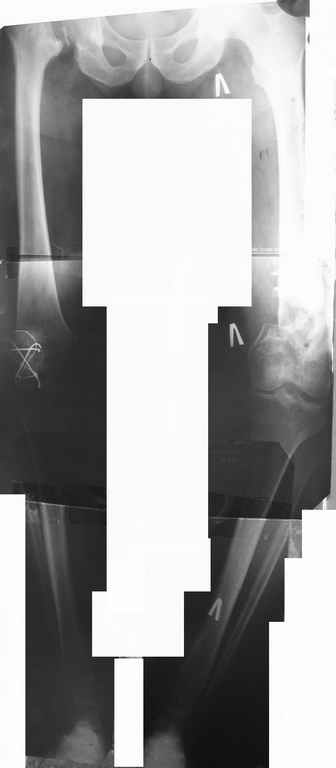

Был оперирован, среди прочего - остеосинтез DHS-фиксатором чреcшеечного перелома правого бедра, DCS-фиксатором остеосинтез оскольчатого чрезмыщелкового перелома левого бедра. Однако, в связи с развитием гнойного коксита были вынуждены убрать DHS-фиксатор и головку. Гнойный свищ правого тазобедренного сустава закрылся сразу после операции. Из-за вторичного смещения и поломки винтов пришлось удалить DCS-фиксатор и сращивать левое бедро внешней иммобилизацией. Прошло чуть более года. Пациент ходит с опорой на обе ноги,пользуется палочкой. Справа относительное укорочение 3см. Слева варус 33гр., тугой ложный сустав н/3бедра. Движения в коленных суставах почти в полном объёме.Перед нами встали вопросы, с чего начать? Протезирование правого ТБС? Восстановление опорности левой конечности? Воспользоваться-ли для этого интрамдулярным остеосинтезом гвоздём с блокированием с ретроградным введением? Стараться при этом восстановить полностью длину, или оставить на потом, на аппаратное решение? Или сразу попытаться использовать аппарат Илизарова? Но боимся потерять колено? Вопросов много.С благодарностью выслушаем все мнения.Заранее спасибоРахматуллин Ринат НургаяновичГКБ N 13 г.Уфа.

Ринат привет из Хабаровки. Я бы начал с правой ноги - там осбых вариантов нет - эндопротез тотальный и быстро возможно подпереть эту ногу полностью (2 месяца и пошел). Риски умеренные (имею в виду инфекцию). Затем сразу перейти на вторую ногу - там работы побольше и в плане вмешательств и в плане сроков востановления опоры и движения. Выбор фиксатора и технологии за Вами - чем лучше владеете - то и верно. Программа - 1. корекция оси, 2.сращение и 3.свободные движения в колене.

Коллега Рыков предлагает начать с него, но хорошо ли, если нога с эндопротезом потом будет перегружаться, будучи единственной опорной на время лечения второй ноги? Может, сначала окончательно восстановить опорность левой, а потом протезировать справа?